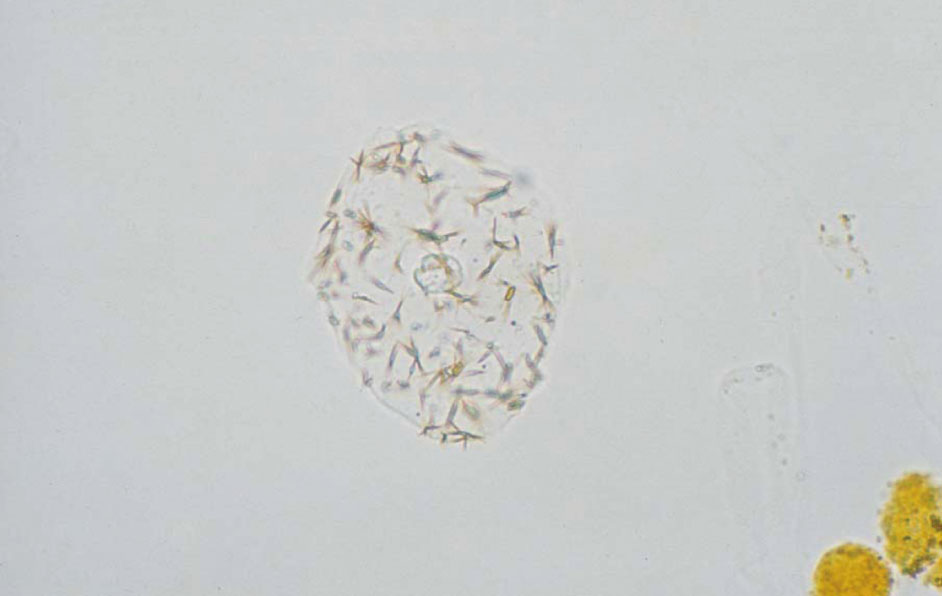

2,8-ジヒドロキシアデニン結晶 40× 無染色

2,8-Dihydroxyadenine crystals 40× No staining

褐色で円形の結晶である。先天性プリン代謝異常のAPRT欠損症でみられる。水酸化カリウムで溶解する。pH 7.0

Brown, circular crystals found in cases of APRT deficiency of congenital purine metabolism abnormality. They dissolve in potassium hydroxide. pH 7.0